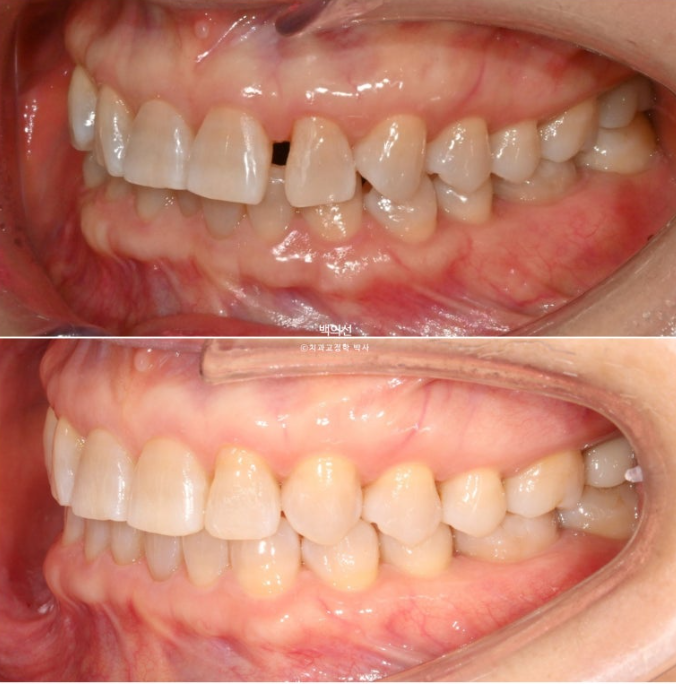

25년 2월, 교정치료를 위해 내원한 환자분입니다.

위 앞니 사이가 점점 벌어지고 아래 앞니는 점점 틀어진다 라는 이유로 오셨습니다.

25.02

앞니가 깊게 물리는 과개교합이 보입니다.

앞니의 뻗침이 있습니다.